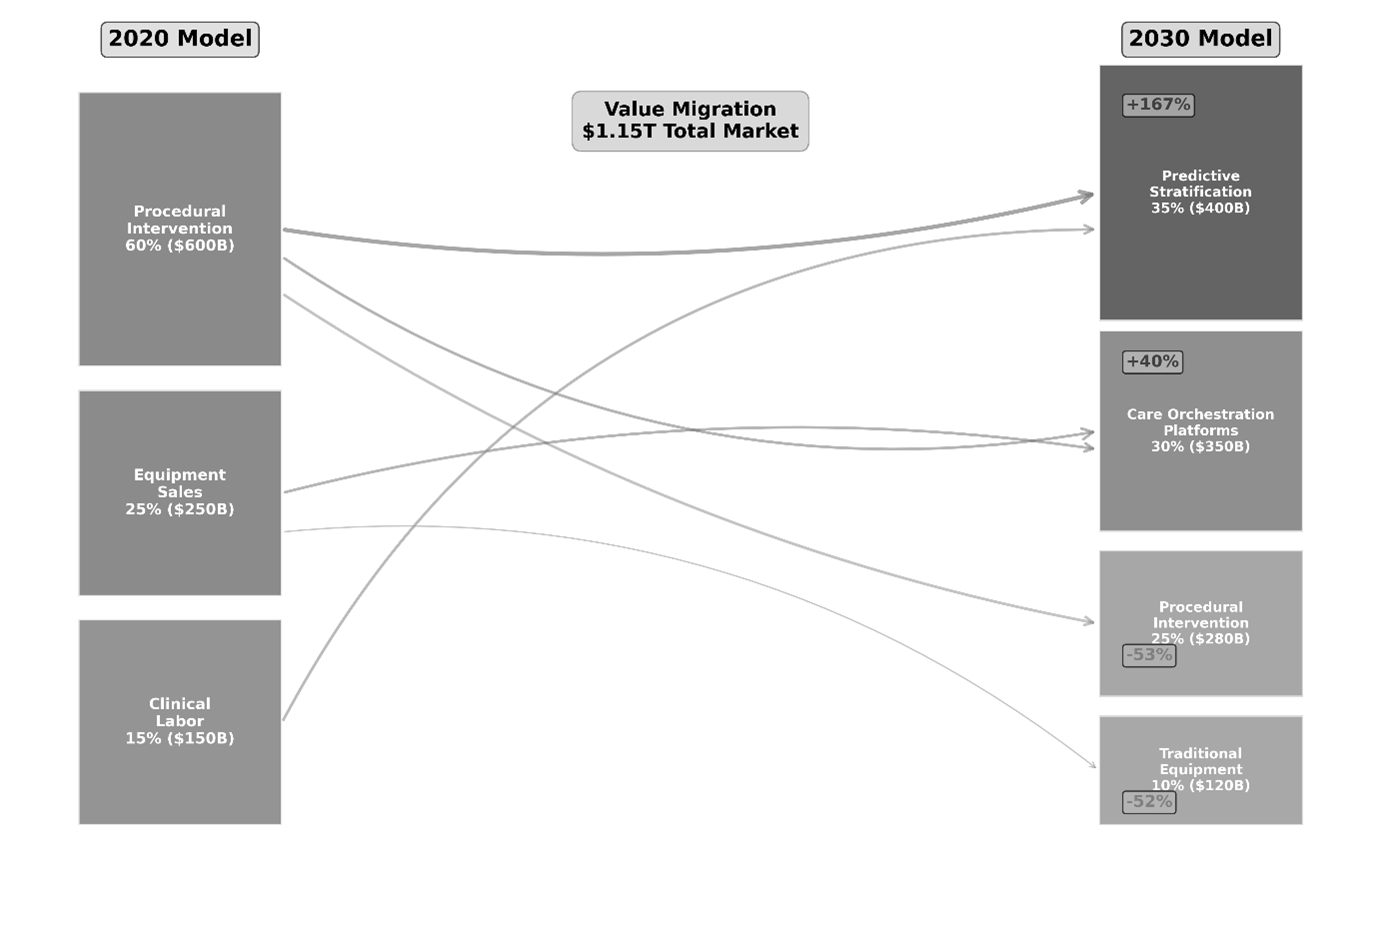

The counterintuitive reality is that diagnostic precision has commoditized. With regulatory pathways accelerating and algorithmic performance exceeding human baseline metrics across multiple specialties, superior accuracy alone provides no sustainable advantage. The new competitive axis is systemic integration. Point solutions represent liability; coordinated diagnostic ecosystems that autonomously stratify, route, and sequence patient interventions constitute defensible strategic positioning.

With diagnostic precision commoditized, capital allocation priority shifts toward domains where competitive differentiation remains achievable. The market presents substantial opportunity in care coordination governance and execution infrastructure.

Pre-Symptomatic Risk Stratification: Capturing the “Pre-Patient”

Conventional diagnostic frameworks operate reactively, engaging after symptom manifestation. The emerging value frontier involves synthesizing genetic predisposition data with longitudinal imaging patterns to project disease probability trajectories before clinical presentation. This approach relocates health system engagement earlier in the patient journey, effectively expanding the addressable market into pre-disease populations.

Figure 3: Healthcare Value Migration (2020-2030) – Margin capture shifting toward predictive stratification.